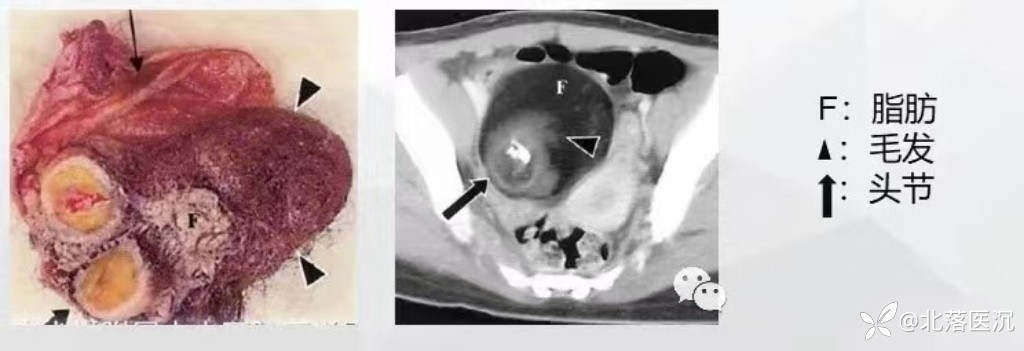

2.肿瘤以单囊为主,亦可为多囊,囊内含毛发和皮脂样物,囊壁内常有一个或数个乳头状突起(头结节),表面有毛发和牙齿长出,头结节切面可见骨、软骨及脂肪组织。

3.根据瘤内脂肪组织的含量,其分为以液性为主型、液脂型、头节型、脂肪瘤型和囊肿型。

4.脂肪为其特征性的影像表现,大于90%的畸胎瘤含脂肪组织。

5.头结节:通常单个,呈类圆形,与囊壁成锐角相交;头结节中可见脂肪、钙化或有毛发附着;头结节是恶变的好发部位,如果直径>5cm的实性头结节、有明显强化并于囊壁成钝角相交的征象要考虑恶变。

CT表现:呈囊性,外形一般为圆形或类圆形,其内可见特征性脂肪密度影、头结节、钙化灶、牙齿等